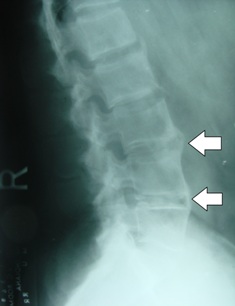

Ankylosing spondylitis may cause eventual fusion of the spine, resulting in a partial or complete rigidity of the spine.

A thorough clinical examination sometimes with xrays is vital for your best outcome of care.